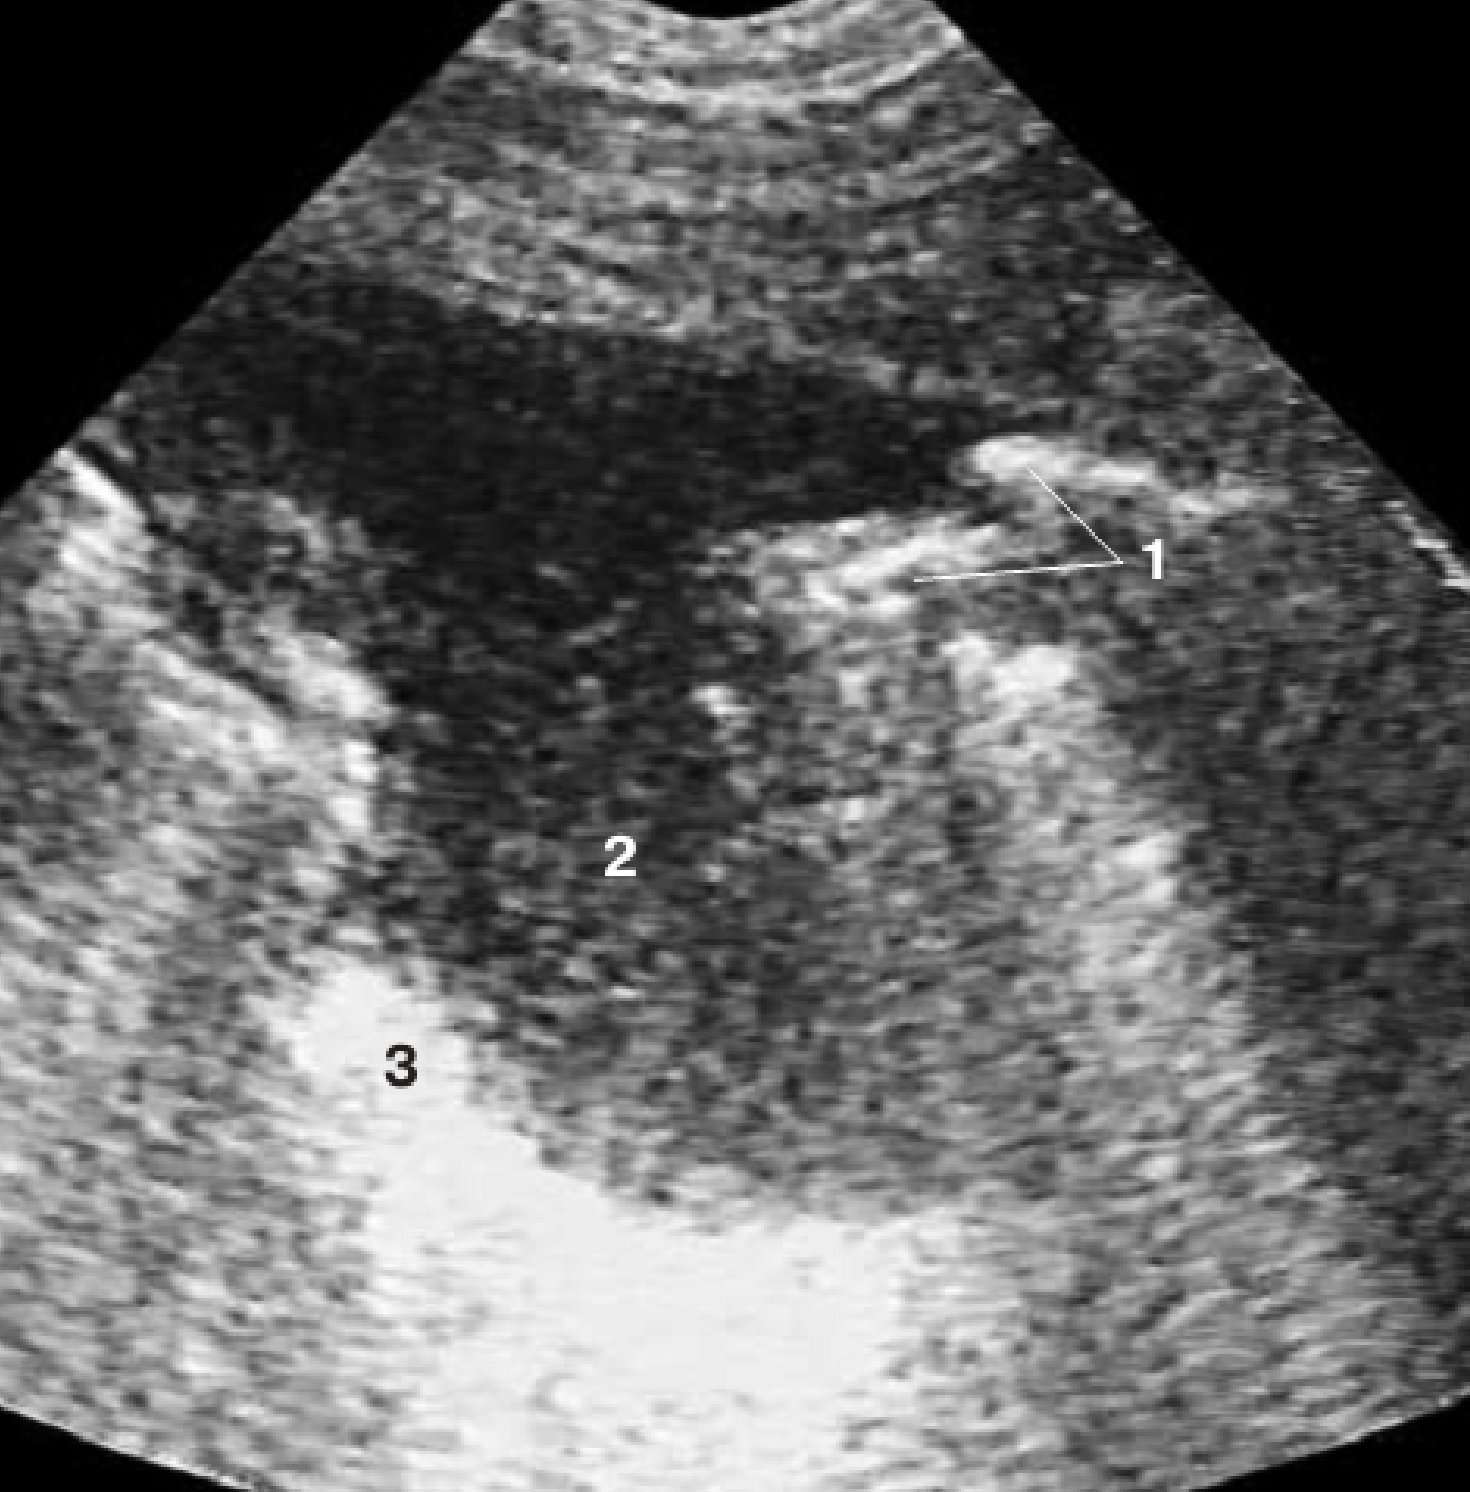

Прогрессирование

деструктивного

процесса

с отсутствием признаков формирования пиогенной капсулы (а);

сообщение полости гнойника с одним из бронхов (б).